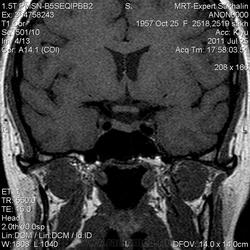

Как мы "динамичим"гипофиз

Женщина.6 лет назад выявлено образование левой доли нейрогипофиза.Пришла на контроль.

Постконтраст

Мне самой показался случай не совсем ясным, но динамик четко показывает участок с отставанием в контрастировании, воронка смещена вправо-о чем  думать бедному начинающему специалисту?

Кстати, немного о внимательности-номера протоколов могут многое подсказать!